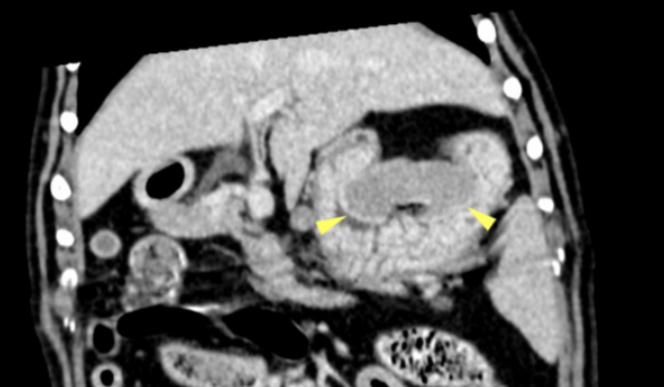

There was an approximately 4cm soft tissue mass located in the bladder trigone (Images 1 – 2). The mass dislocated the right ureter abaxially and dorsally, but was not causing obstruction. There was a large, approximately 7cm x 7cm x2cm parietal mass in the cranial wall of the gastric fundus. The mass protruded into the gastric lumen and was accompanied by an alteration of gastric wall layering (Image 3). A smaller mass was identified in the wall of the greater curvature of the stomach, measuring approximately 4cm x 1cm. The cranial abdominal lymph nodes were enlarged and hypoattenuating (Image 4). No other abnormalities were seen.

Image 3: Dorsal reconstruction of a post-contrast scan showing a large mass in the gastric fundus (arrowheads).